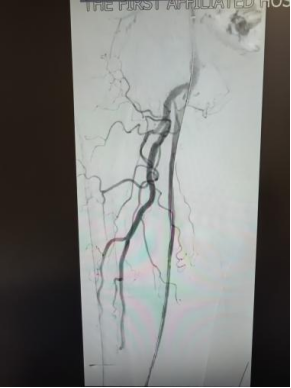

面对严峻病情与家属的殷切期盼,血管外科团队高度重视,联合老年医学科、康复医学科、重症医学科等多学科进行周密会诊评估,反复研判手术方案,精准把控手术指征与风险节点,制定出个体化手术方案。在充分术前准备与严密术中监护下,手术团队凭借精湛技术,为患者开通闭塞血管,恢复下肢血供。

术后,医护团队实行专人专护、精细化管理,从病情监测、疼痛管理、营养支持到康复指导全程跟进。在精心治疗与悉心照料下,患者下肢疼痛明显缓解,缺血症状逐步改善,精神状态日渐好转,避免截肢,重新恢复站立与行走能力。